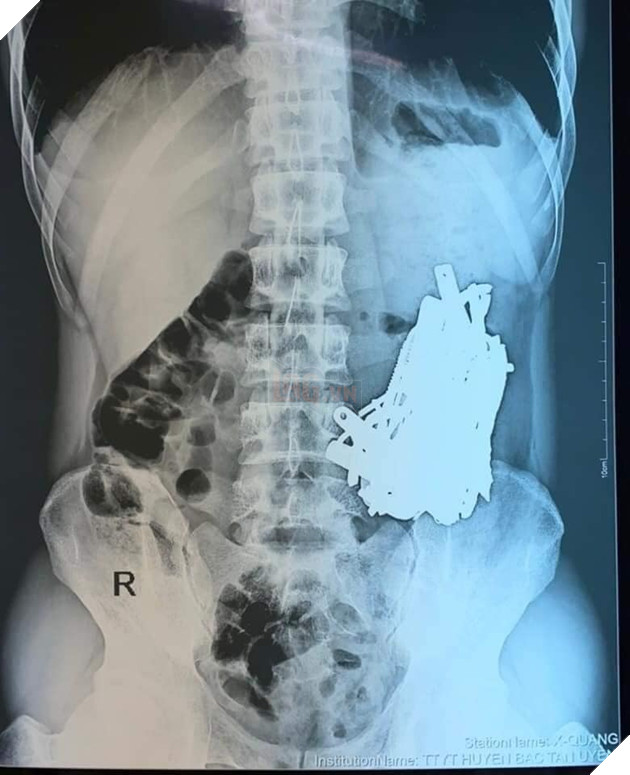

Ảnh chụp phim cho thấy một búi dị vật rất lớn ở phần bụng trái của bệnh nhân

Trong quá trình thực hiện phẫu thuật, các y bác sĩ đã lấy ra khoảng 1kg dị vật kim loại trong bụng nam thanh niêm. Trong đó, một số đã bị ăn mòn một phần, bao gồm nhiều thứ khủng khiếp như đinh, thìa, bấm móng nay, lưỡi dao, thỏi sắt, móc đồ...